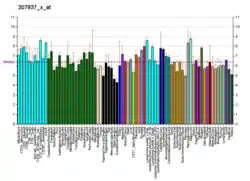

Somatic mutations and epigenetic changes in the expression of the FGFR1 gene occur in and are thought to contribute to various types of lung, breast, hematological, and other types of cancers.

Lung cancers

Amplification of the FGFR1 gene (four or more copies) is present in 9 to 22% of patients with non-small-cell lung carcinoma (NSCLC). FGFR1 amplification was highly correlated with a history of tobacco smoking and proved to be the single largest prognostic factor in a cohort of patients suffering this disease. About 1% of patients with other types of lung cancer show amplifications in FGFR1.[9][10][16][17]

Breast cancers

Amplification of FGFR1 also occurs in ~10% of estrogen receptor positive breast cancers, particularly of the luminal subtype B form of breast cancer. The presence of FGFR1 amplification has been correlated with resistance to hormone blocking therapy and found to be a poor prognostic factor in the disease.[9][10]

Hematological cancers

In certain rare hematological cancers, the fusion of FGFR1 with various other genes due to Chromosomal translocations or Interstitial deletions create genes that encode chimeric FGFR1 Fusion proteins. These proteins have continuously active FGFR1-derived tyrosine kinase and thereby continuously stimulated the cell growth and proliferation. These mutations occur in the early stages of myeloid and/or lymphoid cell lines and are the cause of or contribute to the development and progression of certain types of hematological malignancies that have increased numbers of circulating blood eosinophils, increased numbers of bone marrow eosinophils, and/or the infiltration of eosinophils into tissues. These neoplasms were initially regarded as eosinophilias, hypereosinophilias, Myeloid leukemias, myeloproliferative neoplasms, myeloid sarcomas, lymphoid leukemias, or non-Hodgkin lymphomas. Based on their association with eosinophils, unique genetic mutations, and known or potential sensitivity to tyrosine kinase inhibitor therapy, they are now being classified together as clonal eosinophilias.[6] These mutations are described by connecting the chromosome site for the FGFR1 gene, 8p11 (i.e. human chromosome 8's short arm [i.e. p] at position 11) with another gene such as the MYO18A whose site is 17q11 (i.e human chromosome 17's long arm [i.e. q] at position 11) to yield the fusion gene annotated as t(8;17)(p11;q11). These FGFR1 mutations along with the chromosomal location of FGFR1A's partner gene and the annotation of the fused gene are given in the following table.[18][19][20]

Acquired abnormalities if the FGFR1 gene are found in: ~14% of urinary bladder Transitional cell carcinomas (almost all are amplifications); ~10% of squamous cell Head and neck cancers (~80% amplifications, 20% other mutations); ~7% of endometrial cancers (half amplifications, half other types of mutations); ~6% of prostate cancers (half amplifications, half other mutations); ~5% of ovarian Papillary serous cystadenocarcinoma (almost all amplifications); ~5% of colorectal cancers (~60 amplifications, 40% other mutations); ~4% of sarcomas (mostly amplifications); <3% of Glioblastomas (Fusion of FGFR1 and TACC1 (8p11) gene); <3% of Salivary gland cancer (all amplifications); and <2% in certain other cancers.[11][26][27]